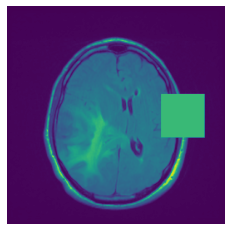

In figure 3, we present qualitative examples of different masking strategies. It is observed that, unlike context prediction and restoration, our method tends to propose targeted masks like the tumor regions or regions with abnormalities and avoids masking less helpful regions. However, it should be noted that Intelligent-Masking does not necessarily mask the tumor regions but considers all areas of interest that results in better feature learning. Examples of other masking samples are provided in supplementary materials. Furthermore, in medical images, unlike natural scenes, the structures are very local with imbalanced information throughout an image. Therefore, random masking strategies as shown in Fig 3 operate ineffectively by masking non-informative regions.

Figure 2: Qualitative examples of compared method’s strategies for masking

Figure 3: More qualitative examples of different distorting strategies including our method. We show the different self-supervised mechanisms on both datasets of MR (rows: 1-3) and ultrasound (rows: 4-6) images for lower-grade glioma and breast cancer diagnosis respectively. We include both images of normal (rows: 1,4) and cancer (rows: 2,3,5,6) conditions for each dataset. We also observe that our method treats each image based on its context information with no predetermined strategy.